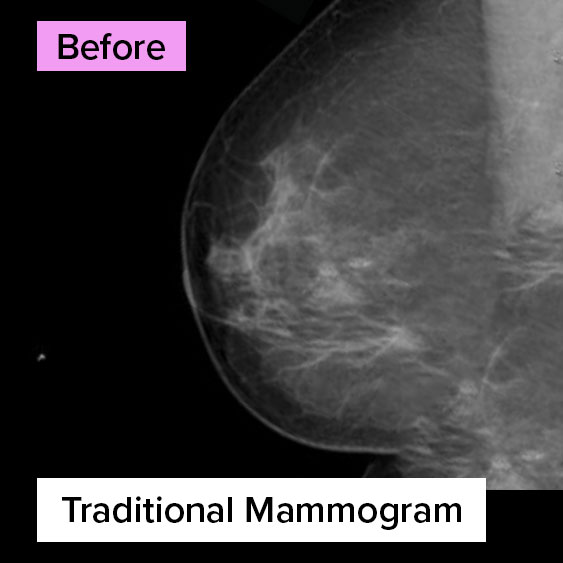

Before After

Same Breast. Different Technology.